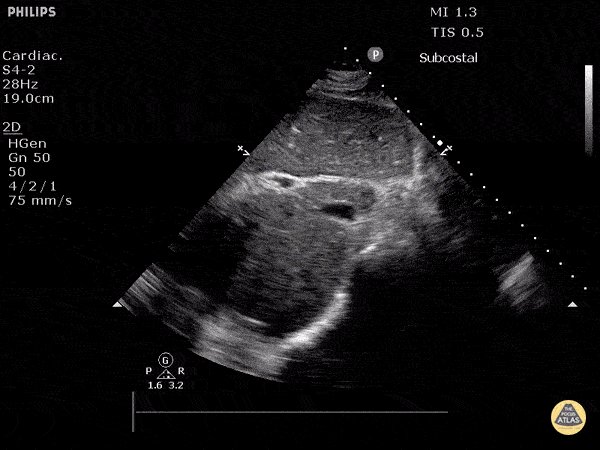

(1/6): 5 myths of IV fluids 🦄 A 🧵that makes my soul cringe. Please help spread the word 🙏#stopinhospitaldrowning